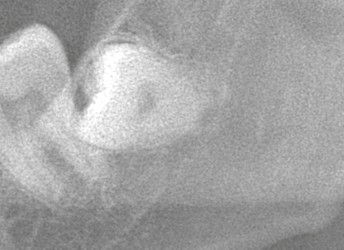

特に下顎の埋伏親知らずでは、腫れや痛みの経過が気になりますよね。

今回は、**埋伏抜歯を前提にした“現実的な経過とスケジュール”**を解説します。